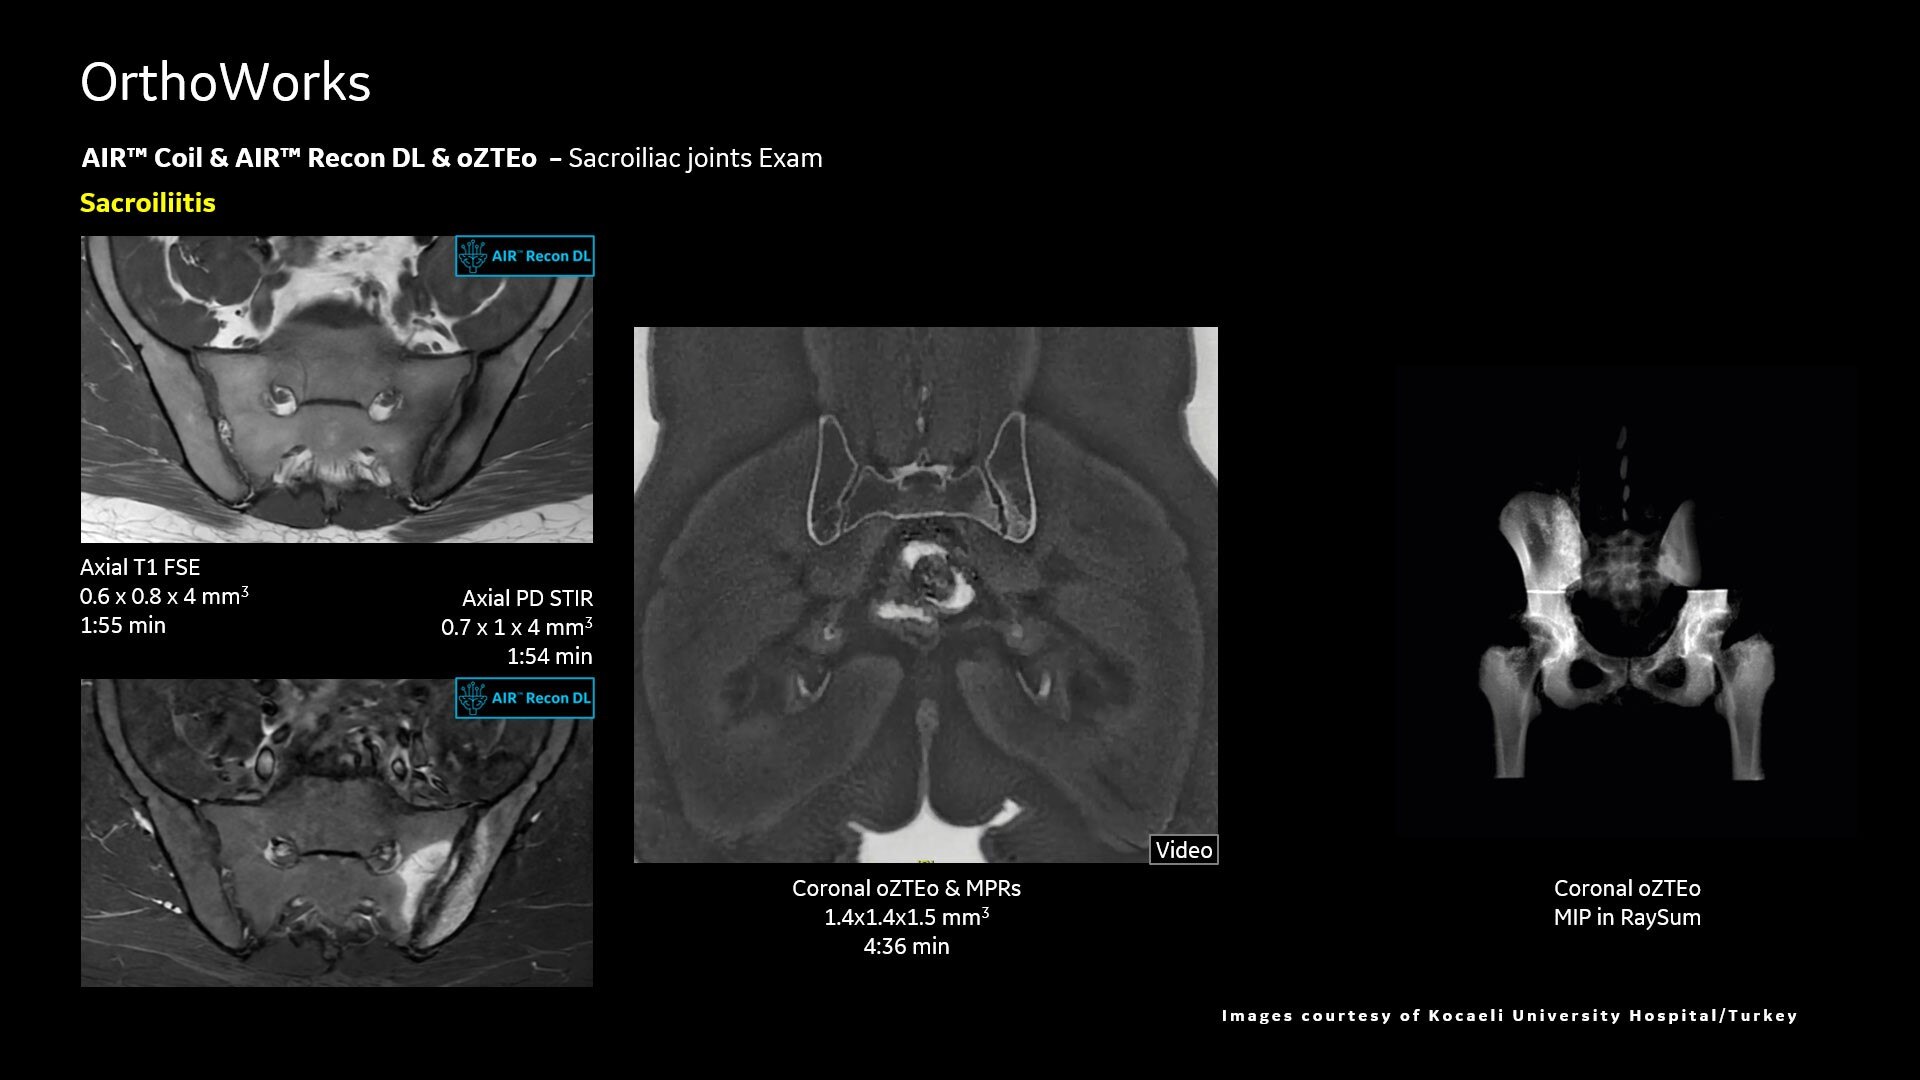

Adaptive AIR™ Coils accommodate all types of scans and patient sizes

AIR™ Recon DL improves SNR and image sharpness, enabling shorter scan times

Up to 50% faster acquisition time with AIR™ Recon DL